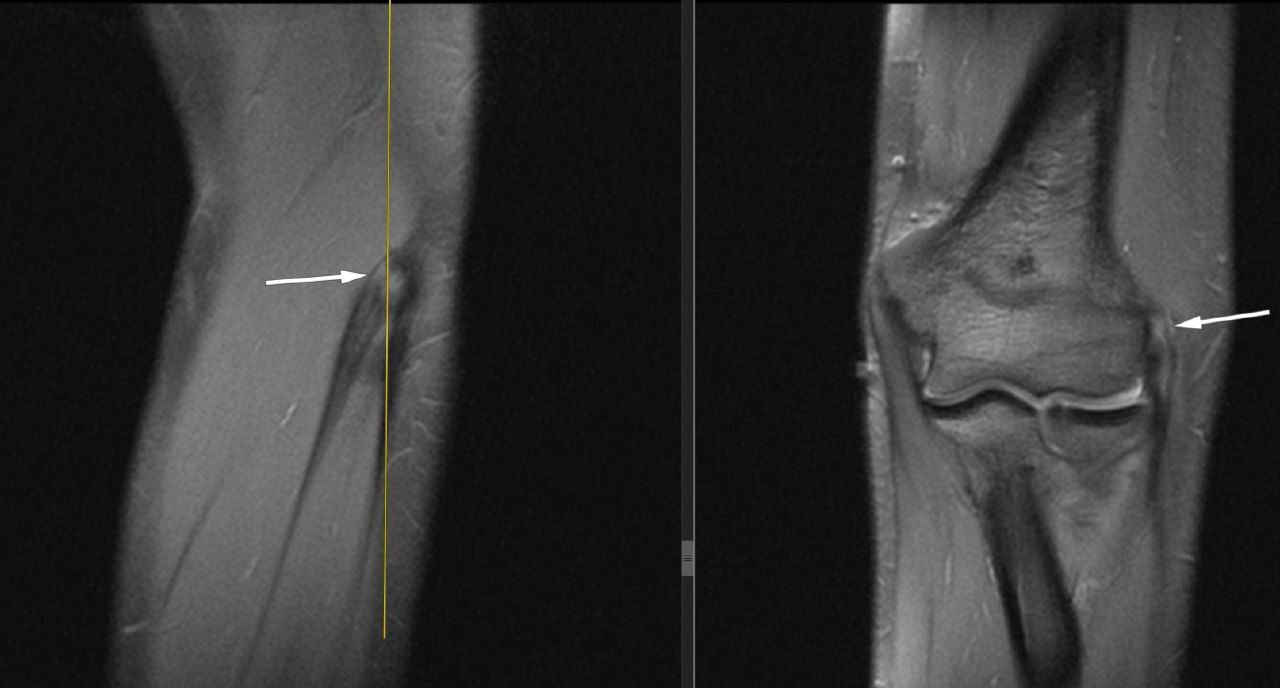

Это хроническое перетруживание сухожилий мышц предплечья, выполняющих сгибание в локтевом, разгибание в лучезапястном суставах и поворот кисти ладонью вверх (супинация).

Обычно, болеют люди, работа, которых связана с удерживанием чего-либо и одновременными вращательными движениями предплечья – теннисисты (ракетка), автомеханики, электрики, сантехники, ортопеды (работа отвёртками и гаечными ключами), офисные работники (работа компьютерной мышью), метатели, лучники, стрелки из пистолета и т.д.

При стереотипных резких движениях происходит травмирование сухожилий (нарушение кровоснабжения и структура коллагена) и реактивное воспаление окружающих тканей.